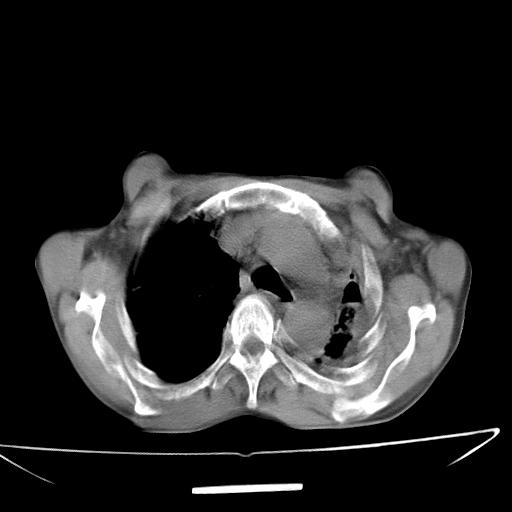

男  70岁,发烧咳嗽4天。盗汗,消瘦。无痰中带血丝,以前有肺tb病史,ct见,双肺tb,左侧胸廓塌陷,左胸膜肥厚粘连。纵隔移位,右侧胸腔积液,大家说说那个心影前左肺舌叶除了肺大炮还有炎症还是干酪性肺炎?有占位吗?我看纵隔淋巴结也大。

1)两肺继发性肺结核并左肺上叶肺不张,支气管扩张。2)双侧胸膜炎(胸膜增厚+少量胸腔积液)。

两肺继发性肺结核并感染,左肺上叶肺不张。建议ct增强。